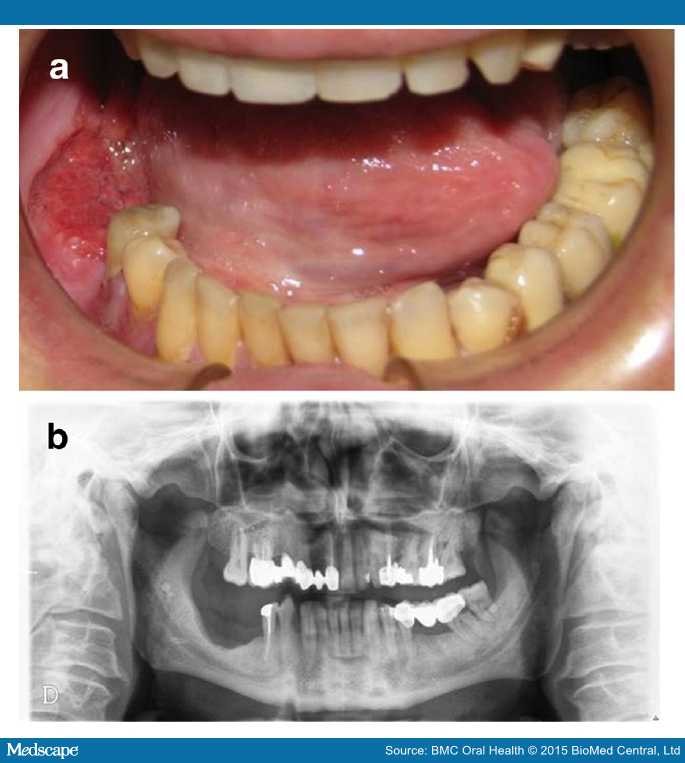

From www.medscape.com

Dental Implant PostSurgery and Radiotherapy for Oral Cancer Page 3 Radiotherapy And Dental Restorations radiotherapy to the head and neck region causes xerostomia and salivary gland. radiotherapy is a widely used treatment modality for managing carcinomas in the head. most head and neck cancers are treated with surgery or radiotherapy or, a combination of both. a team including speech therapist, dietitian, dental specialist, and psychologist along. patients undergoing radiotherapy. Radiotherapy And Dental Restorations.